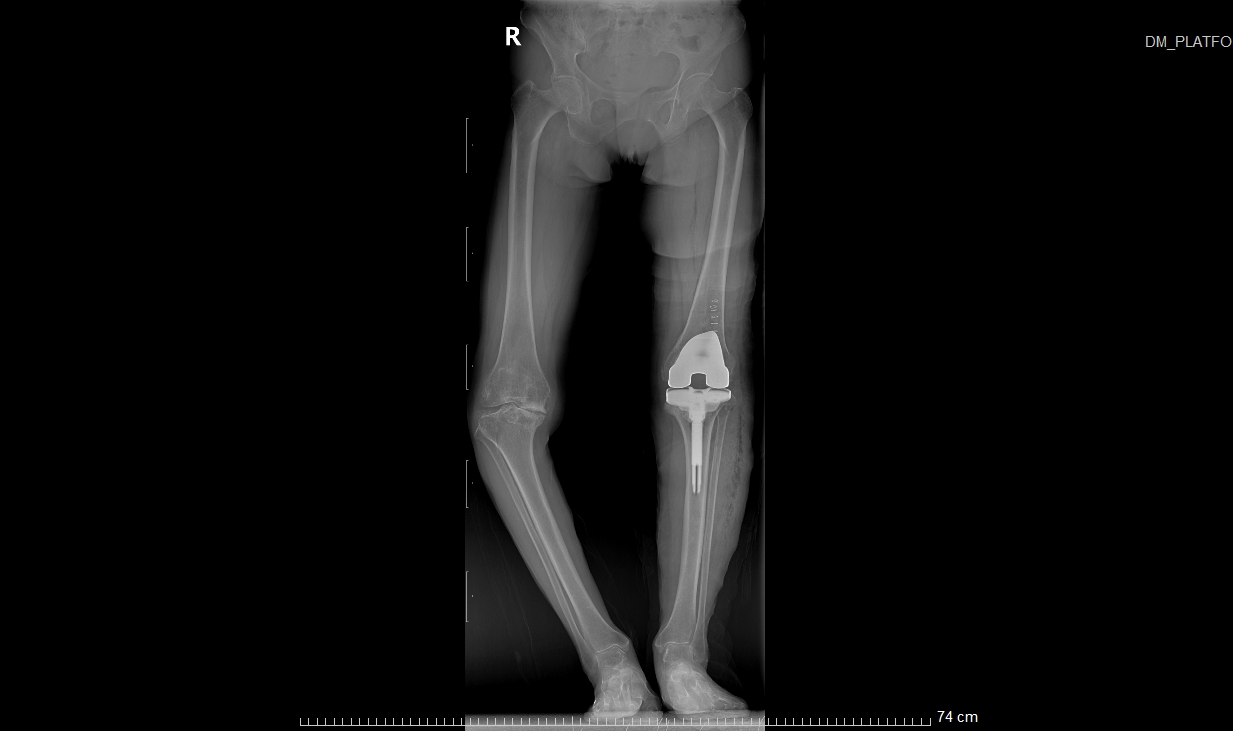

患者术后X光扫描

这个过程可以类比为镶牙,即切除受损部分并替换为金属材料。同理,在膝关节置换术中,医生会移除严重磨损的关节表面软骨及部分软骨下骨,在原位安装与原始膝关节表面形状类似的金属组件(即假体),使用骨水泥将假体与患者自身的股骨和胫骨固定在一起,使之恢复膝关节的正常功能。

患者术前VS术后对比

①站立位X光片中显示关节间隙消失或极度狭窄